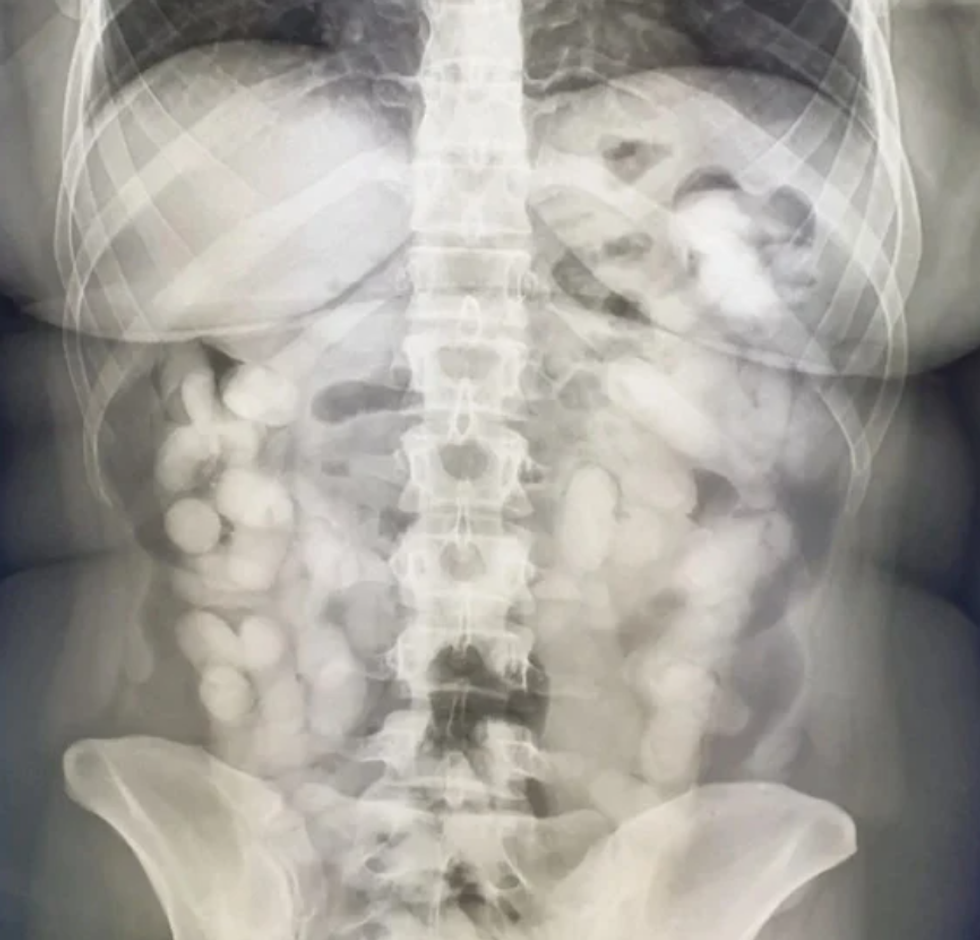

Ajo u veçua nga pasagjerët e tjerë dhe ekzaminimi përcaktoi praninë e drogës në bagazhe. Pas kësaj, ajo u referua për një rreze X, e cila përcaktoi se kishte 76 trupa të huaj në trup, domethënë. kapsulë

Ajo që është interesante është se Andreit iu deshën plot 10 ditë për të "nxjerrë" kapsulat e drogës nga trupi i saj, pavarësisht marrjes së laksativëve të fortë. Pas dhjetë ditësh, u përcaktua se ajo kishte gjithsej 990 gram kokainë në trupin e saj.